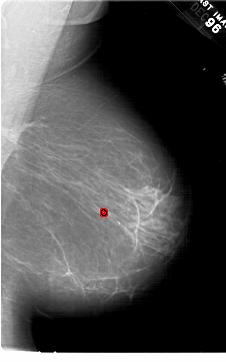

A_1452_1.LEFT_CC

LEFT_CC LINES 6376 PIXELS_PER_LINE 3676 BITS_PER_PIXEL 12 RESOLUTION 43.5 NON_OVERLAY

FILE: A_1452_1.RIGHT_CC.OVERLAY

TOTAL_ABNORMALITIES 1

ABNORMALITY 1

LESION_TYPE CALCIFICATION TYPE PLEOMORPHIC DISTRIBUTION CLUSTERED

ASSESSMENT 4

SUBTLETY 4

PATHOLOGY BENIGN

TOTAL_OUTLINES 1